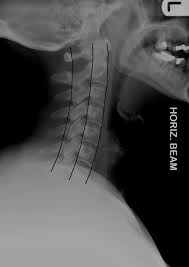

This procedure may be used to diagnose back or neck pain, fractures or broken bones, arthritis, degeneration of the disks, tumors, or other problems. Enter search terms and tap the search button. They show pictures of your internal tissues, bones, and organs. Please understand that our phone lines must be clear for urg. Here's what to expect with this painless procedure and why your dentist may recommend it.

This procedure may be used to diagnose back or neck pain, fractures or broken bones, arthritis, degeneration of the disks, tumors, or other problems. It's commonly done after someone has been in an automobile or other accident. They show pictures of your internal tissues, bones, and organs. Here's what to expect with this painless procedure and why your dentist may recommend it. Please understand that our phone lines must be clear for urg. Enter search terms and tap the search button.